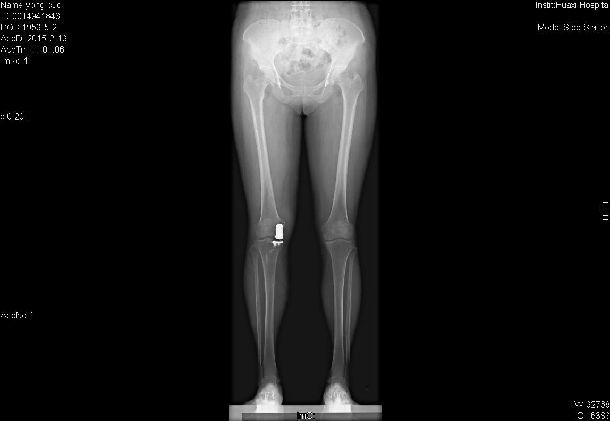

• 换膝盖要花多少钱?膝关节置换手术的优点有哪些?

膝关节位于大腿骨和小腿骨连接处,健康的膝关节能够自由地活动,是因为关节表面覆盖一层滑润的软骨组织和关节周围有强健的肌肉。 软骨是一层光滑的软组织,它覆盖在大腿骨和小

• 膝关节置换手术要花多少钱?关于这台手术你要了解的还有很多……

当所有非药物和药物疗法都无效,骨关节炎已经发展到晚期,患者遭受持续严重的关节疼痛和功能障碍时,可考虑进行关节置换术。医生会根据患者的年龄、体重、活动水平、膝关节大小,形状以及整体健康状况制定手术方案,也不一定换掉整个关节,也可换掉一部分关节(单髁关节置换术),大部分患者手术次日就可下地先走,康复后可很大程度的恢复日常功能和生活质量。不过人工关节毕竟有使用寿命,因此骨关节炎的治疗原则是:从保守无创治